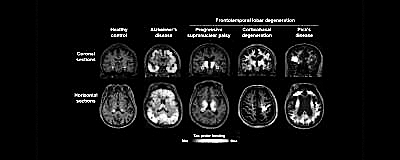

一种新的脑成像示踪剂可以为研究阿尔茨海默病和其他神经退行性疾病的发展提供一扇清晰的窗口。这种示踪剂强调了大脑中有毒tau蛋白的积累,可以区分原本早期阶段难以区分的一系列被称为tau病理学的疾病,比如额颞叶痴呆和进行性核上麻痹。

研究人员在39名患有包括阿尔茨海默病在内的一系列与tau相关疾病的患者身上测试了这种示踪剂。根据脑扫描中示踪剂信号的位置,研究小组能够准确预测疾病的类型,这在后来的尸检中得到了证实。他们的结果10月29日发表在《神经元》杂志上。

在老年痴呆症的发展过程中,tau蛋白的沉积被认为是β淀粉样蛋白斑块积累引起的。尽管大多数针对阿尔茨海默病的疗法都集中在淀粉样蛋白上,但tau蛋白的存在被认为与症状的发展有更密切的联系。研究人员能够根据扫描中tau蛋白的丰富程度,准确预测出17名老年痴呆症患者症状的严重程度。

这种示踪剂可能对除阿尔茨海默病以外的其他疾病产生最大影响。此前开发的实验跟踪器无法检测出tau病理学中常见的所有形式的tau蛋白。“旧示踪剂的一个问题是,阿尔茨海默病的tau病理学可以被检测出来,但在其他tau病理学中检测出它就困难了。这打开了新的视角。现在我们真的可以想象病人的病理,可以把它和症状联系起来。”并未参与这项研究的比利时哈瑟尔特大学的神经科学家Ilse Dewachter说。

在可能由tau蛋白引起的额颞叶痴呆等情况下,早期症状可能是显著的行为改变和丧失抑制能力,从而导致社会问题。“即使没有根治tau蛋白的方法,我们也可以通过预测每个患者出现的症状来帮助他们。这就是脑部tau蛋白沉积成像的主要优势。”